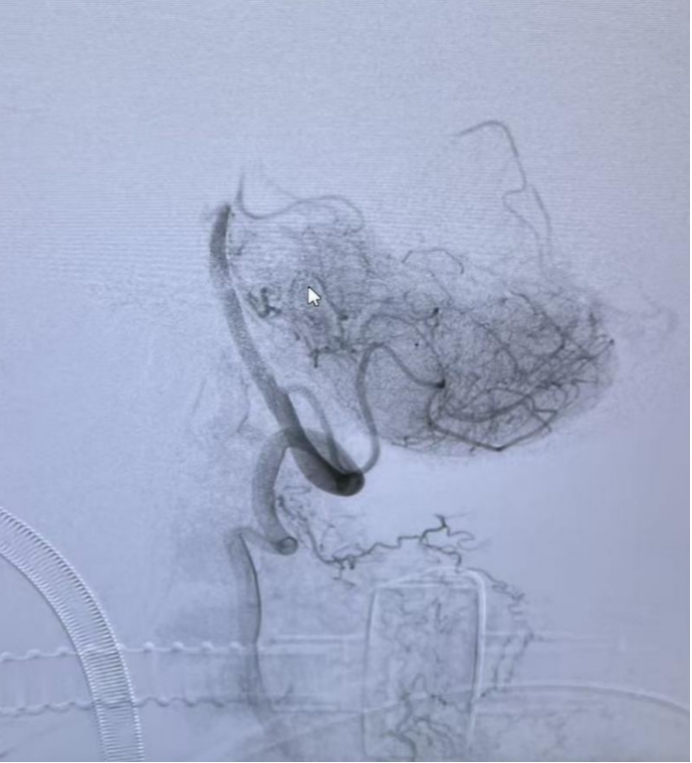

介入团队随即接力上阵,在全麻下进行脑血管造影,清晰显示基底动脉末端闭塞,远端未见明显显影。

面对患者血管迂曲、路径复杂的难题,张显强主任医师和杨超豪主治医师凭借精湛技术,通过抽吸导管精准取出一枚长达10mm的血栓。

造影显示

血管再通良好!

介入手术后血管完全再通